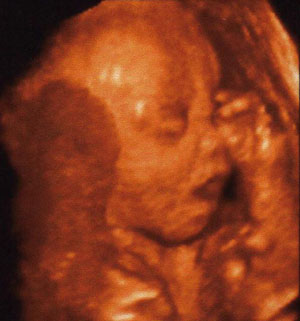

Rakok már fel képet a drágámról.